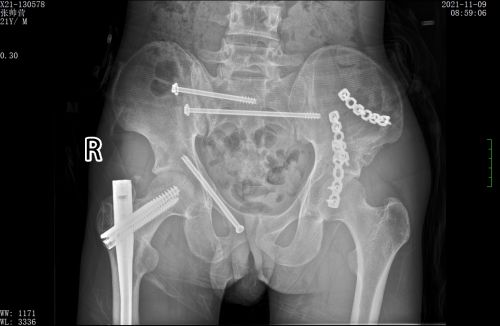

术前x线可见多处骨折。

创伤骨病科主任盛斌指出:患者骨盆存在多处骨折,失血性休克明显,由于此处解剖结构的复杂性和特殊性,传统手术方式往往手术时间长、创伤大、出血多。而如果不能早期对骨盆环进行稳定,骨折端及其他部位的静脉丛可反复出血,导致休克加重,危及生命。患者刚做了开腹手术,如果再进行传统骨折切开复位手术,风险极高。

经过反复讨论研究手术方案,在麻醉科、手术室的配合下,盛斌主任带领创伤救治团队为小张施行复杂骨盆及股骨骨折微创复位内固定手术。术后,在急诊ICU等多学科团队的积极治疗和精心护理下,患者病情好转出院。